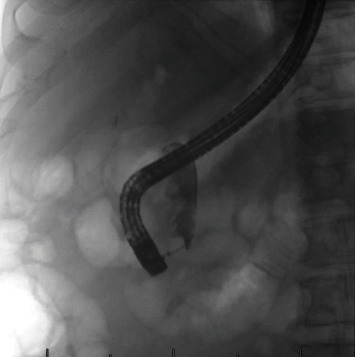

Introduction: Sump syndrome is a rare complication following bilioenteric anastomosis, most commonly following choledochoduodenostomy. This is only the third case in the literature of sump syndrome of the distal common bile duct (CBD) following end-to-side Roux-en-Y choledochojejunostomy (RYCJ). Case Presentation. A 69-year-old man with a history of end-to-side RYCJ for recurrent primary choledocholithiasis presented 3 years postoperatively with right upper quadrant (RUQ) abdominal pain affecting his quality of life. The work up revealed mild leukocytosis and computed tomography (CT) imaging that showed dilation of the distal CBD remnant. He underwent endoscopic retrograde cholangiopancreatography (ERCP) with the removal of large amounts of debris with initial resolution of his pain, but the pain recurred after several months and after two further ERCPs with only short-term resolution of pain, he eventually underwent an open distal CBD excision and the pain has since resolved.

Conclusions: This case report describes a rare case of sump syndrome following RYCJ that presented with abdominal pain alone. Sump syndrome may have a wide array of presenting symptoms, and the pathophysiology of sump syndrome varies based on bilioenteric reconstruction. Although it has rarely been reported to occur in the distal blind CBD remnant following either RYCJ or hepaticojejunostomy, it is important to consider this in the differential for patients with abdominal pain following any bilioenteric reconstruction.